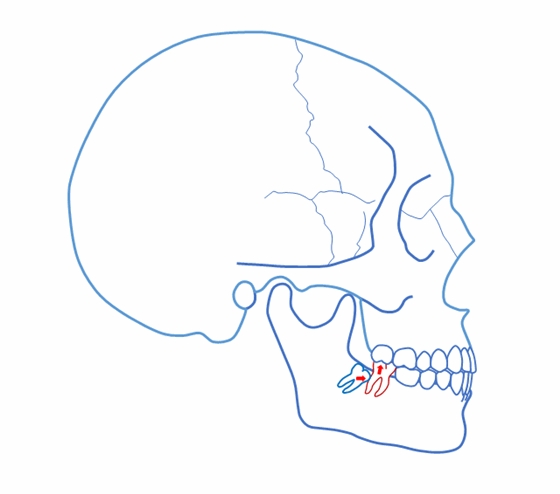

正位萌出到位,在牙尖交錯(cuò)位建立咬合關(guān)系,只是一個(gè)靜態(tài)的狀況??陬M系統(tǒng)的功能要靠運(yùn)動(dòng)來(lái)實(shí)現(xiàn),而一旦動(dòng)起來(lái),很多“看”似建立了正常咬合關(guān)系的智齒很可能會(huì)造成咬合干擾,給整個(gè)口頜系統(tǒng)帶來(lái)傷害。

這樣 “萌出到位有咬合” 的智齒應(yīng)該拔掉